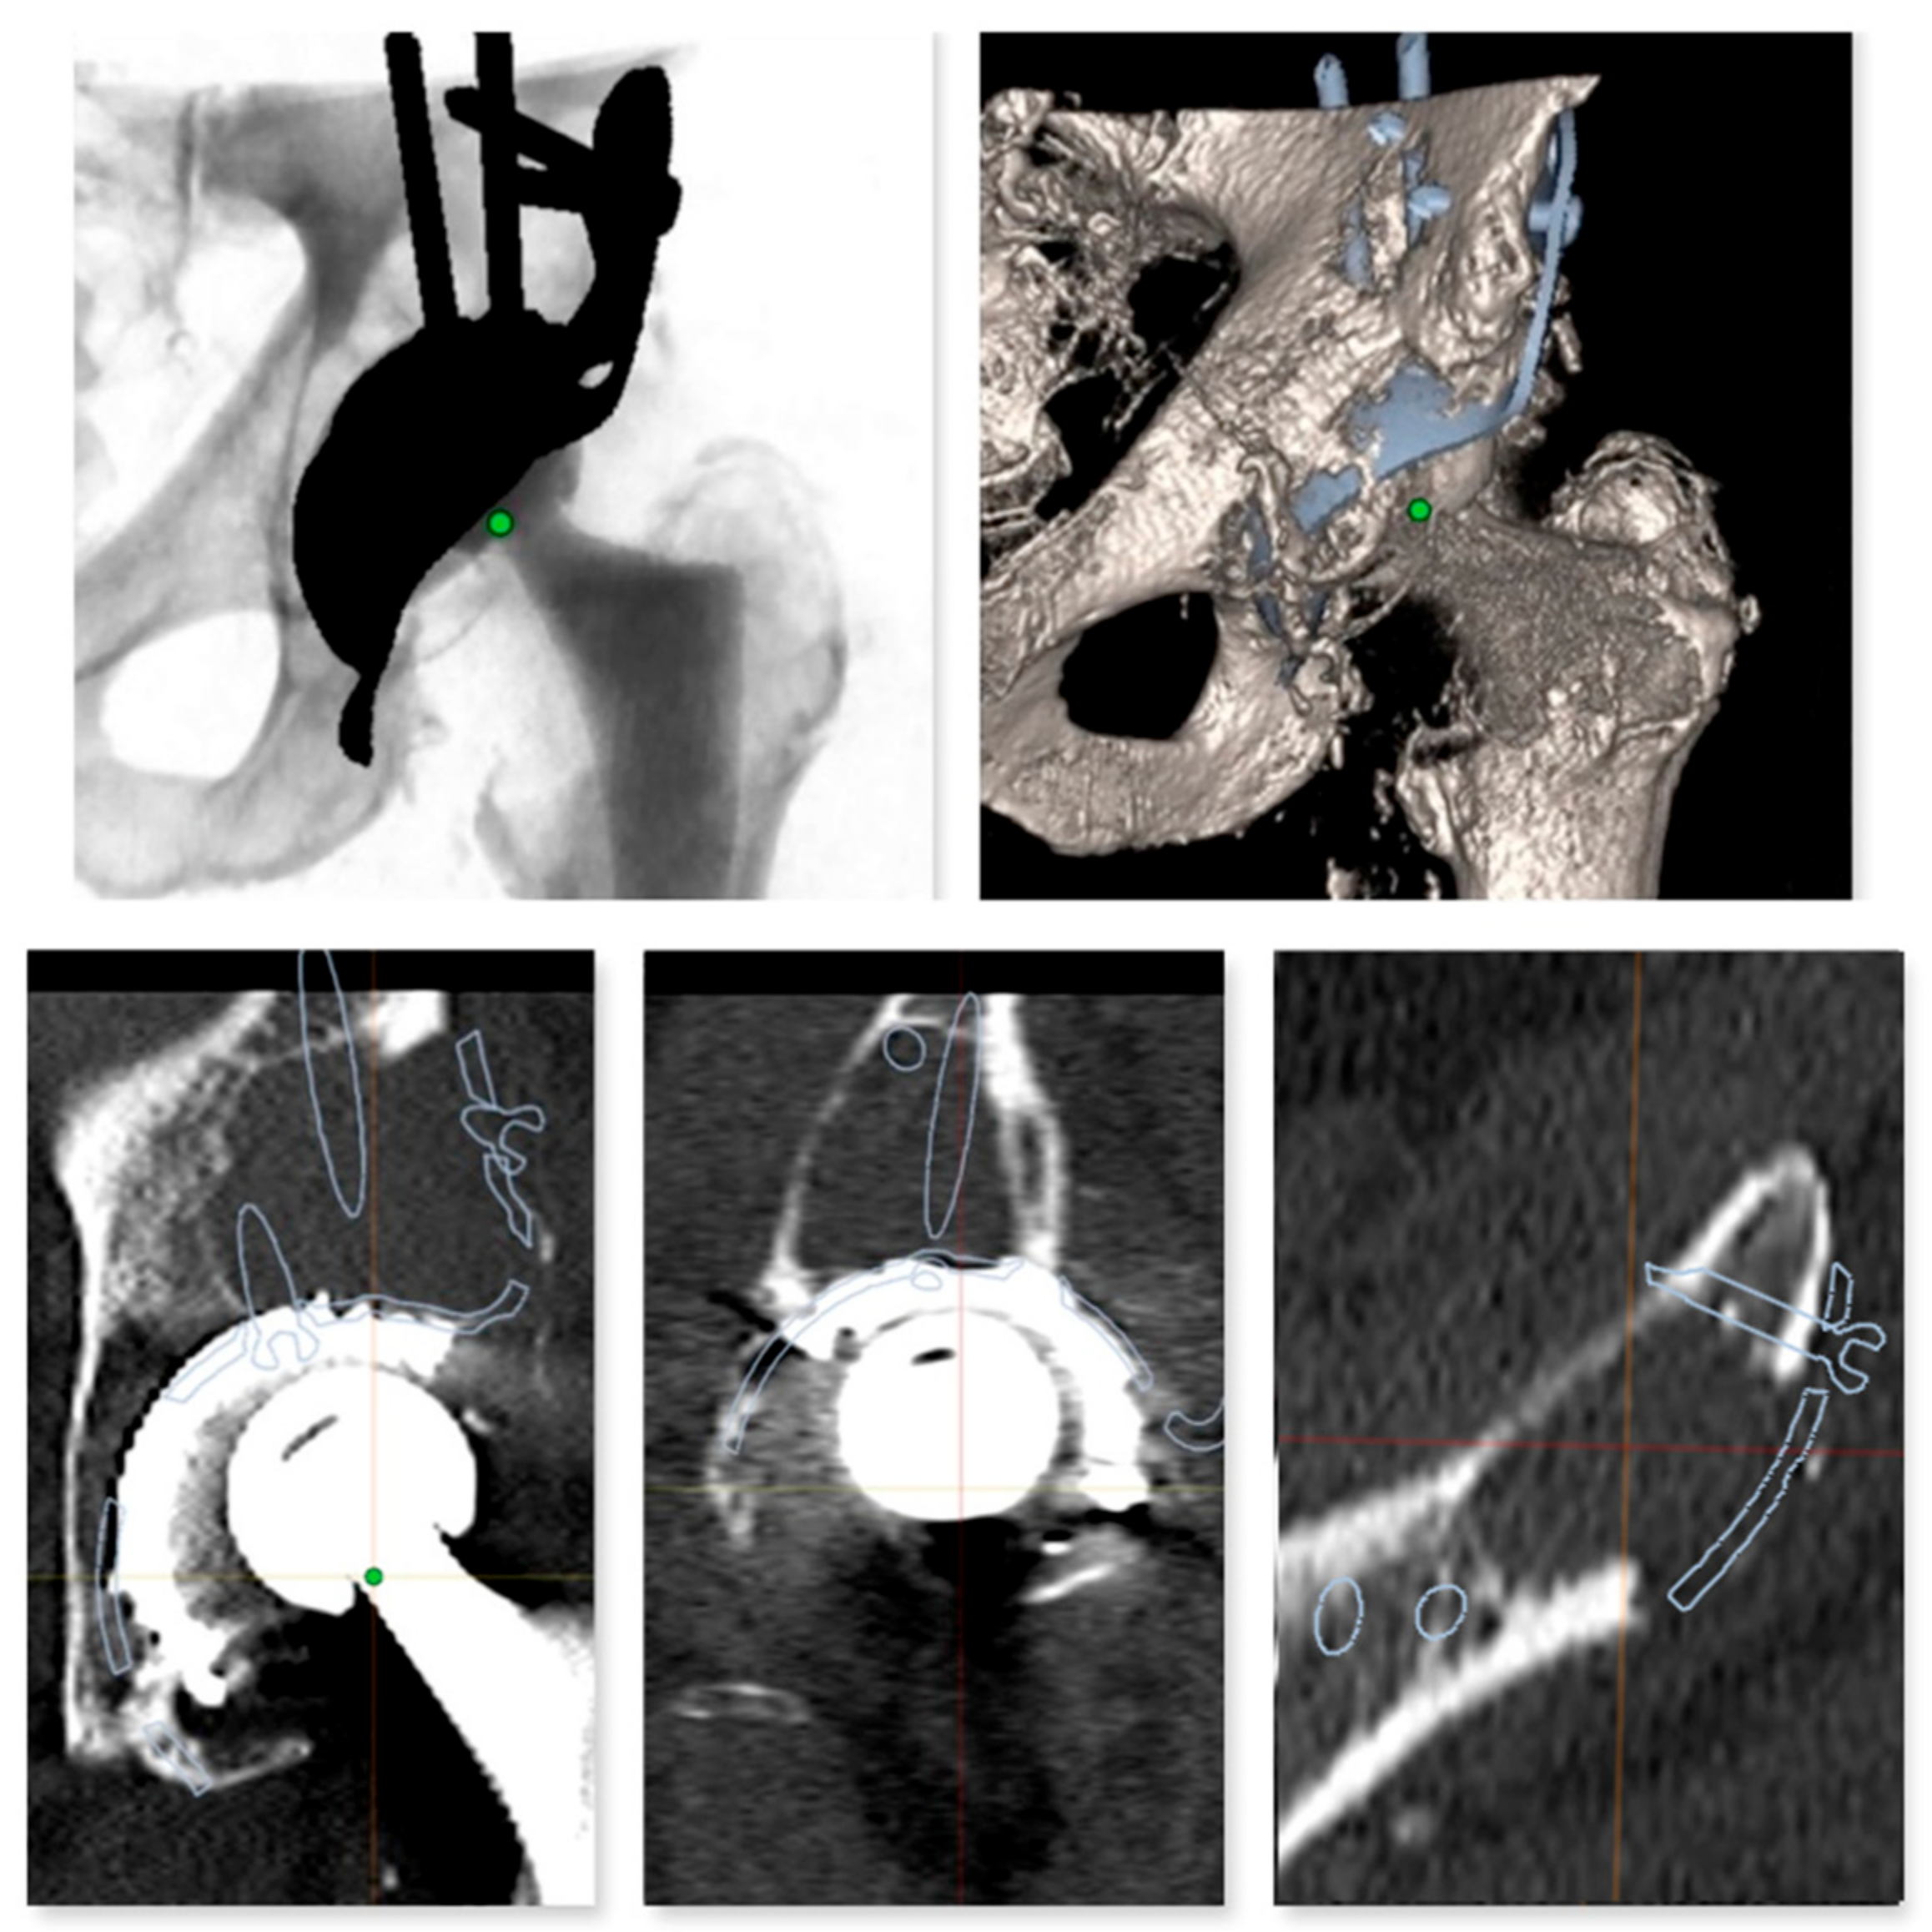

2.2. Digital Templating